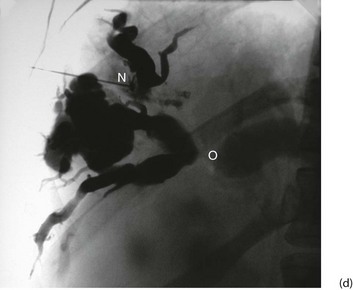

(c) and (d) Percutaneous transhepatic cholangiography

A needle N is passed into the liver until it encounters a dilated duct. Contrast medium is then injected to outline the ducts. (d) Case study—this deeply jaundiced 57-year-old woman has grossly dilated intrahepatic ducts and complete obstruction of the proximal common bile duct in the porta hepatis at O. This was due to lymph node metastases from carcinoma of stomach. This method is employed less often nowadays because of the superior safety of other methods described here